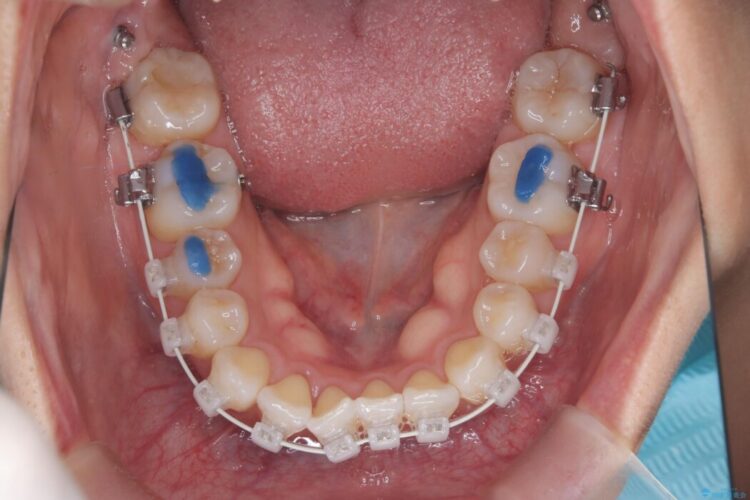

- 矯正装置:ワイヤー(審美装置)

矯正検査の結果、右上7番が頬側に大きくズレており、うまくかみ合っていない状態でした。

全体的にスペース不足ではありましたが、患者様は抜歯をしたくないとのご要望だったため、上顎の裏側に「トランスパラタルアーチ(TPA)」という装置を装着し、奥歯の幅を調整しながらスペースを確保する計画を立案。

矯正装置は目立ちにくい審美ワイヤーを使用しています。

トランスパラタルアーチを用いて右上7番目の歯を内側へ誘導し、正しい位置へと修正しました。